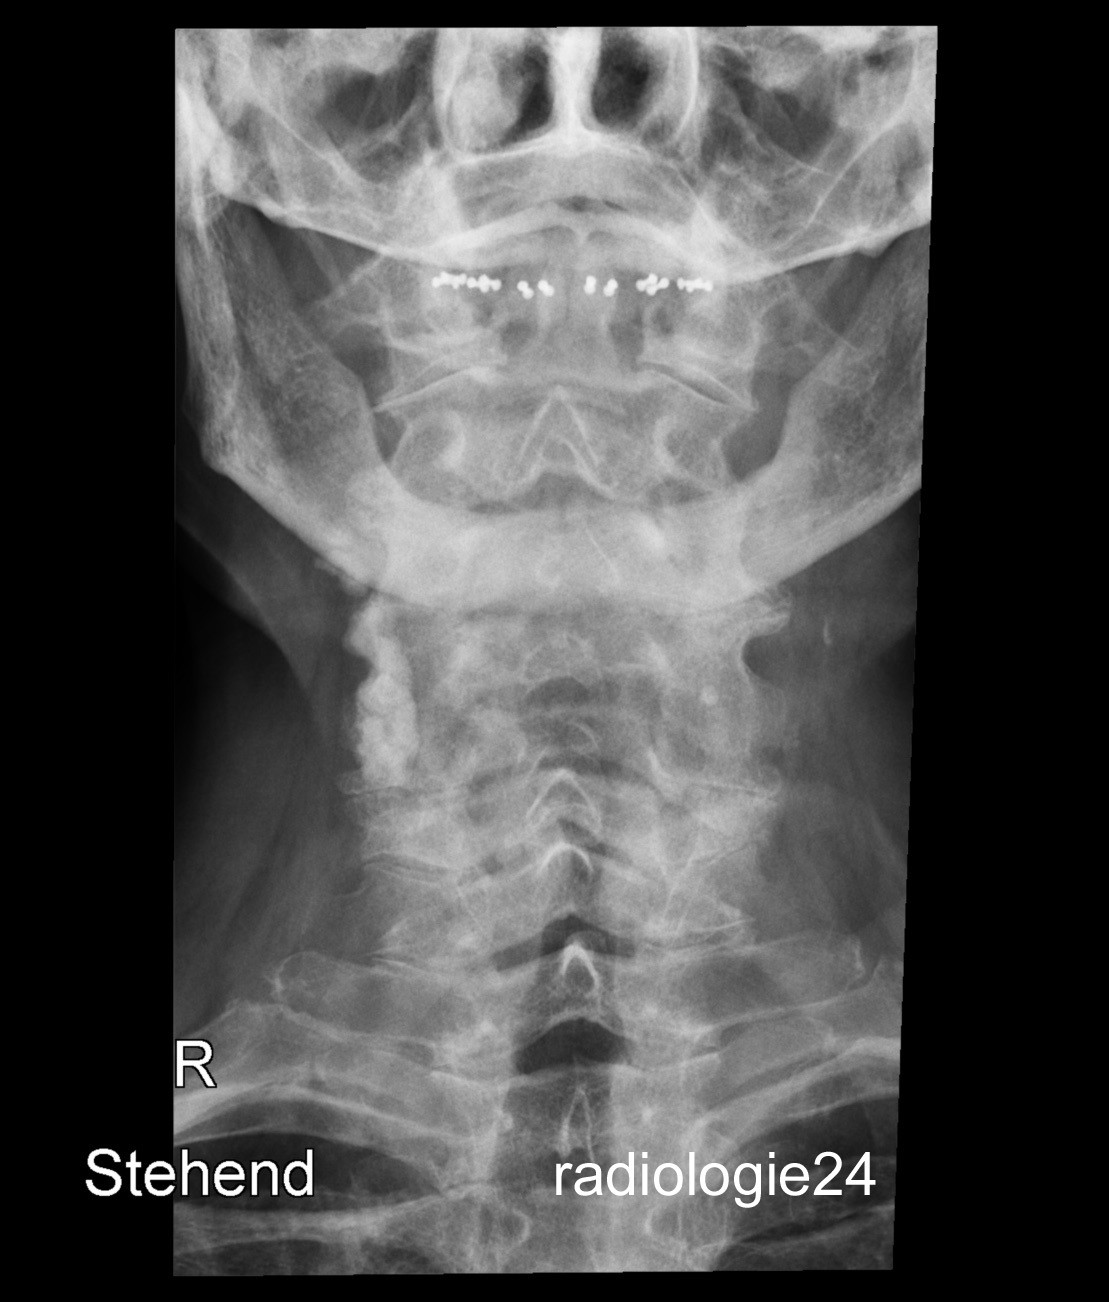

Röntgenfall des Monats Juli 2018 mit Auflösung

79 jähriger Patient Z.n. Sturz mit dem Velo auf den Kopf. Schmerzen HWS? Ihre Diagnose? Weitere radiologische Diagnostik?

Bild vergrössern

Link zur Auflösung mit ausführlichem Befund:

https://www.radiologie24.ch/radiologie-mediathek/roentgenfall_des_monats